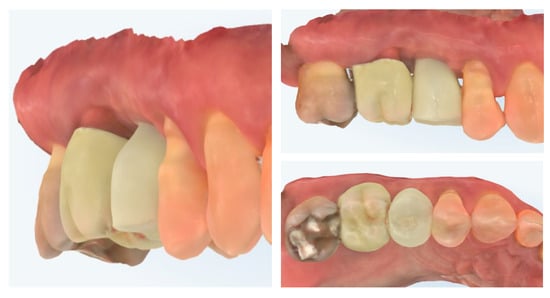

Digital scans obtained at delivery of the definitive prosthetic reconstructions show stable integration of both the implant-supported crown in region 15 and the full-contour zirconia crown on tooth 16 (Figure 17). The emergence profile of the implant-supported crown completely copies the profile of the temporary crown in order to not induce changes in the crestal bone. The peri-implant soft tissues demonstrate healthy contours and harmonious adaptation to the restoration’s emergence profile. The occlusal and proximal relationships are well-preserved, ensuring functional loading and esthetic integration with adjacent teeth. No soft tissue recession or volumetric loss is evident, confirming the stability of the roll flap augmentation and the favourable outcome of the prosthetic phase.

Figure 17.

Clinical view of the final implant-supported and tooth-supported crowns (8 months post-op).

Clinical view at 6 months following delivery of the definitive prosthetic restorations demonstrates stable peri-implant and periodontal soft tissues (Figure 18). The mucosal margin is healthy, with adequate buccal thickness and harmonious integration of the implant-supported crown in region 15 and the adjacent tooth-supported crown in region 16. No signs of inflammation, mucosal recession, or soft tissue collapse are evident, confirming long-term stability of the roll flap augmentation and successful functional and esthetic rehabilitation. The X-ray control shows stable crestal bone levels.

Figure 18.

Clinical appearance and X-ray control 6 months after definitive prosthetic treatment (14 months post-op).